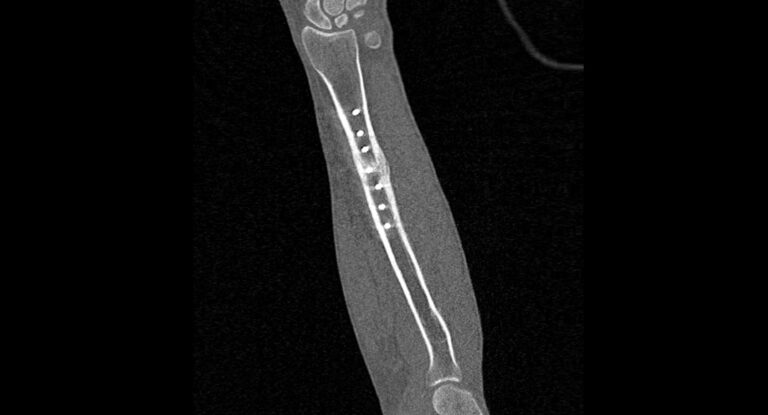

Мультиспиральная компьютерная томография является наиболее точным и информативным методом диагностики патологии предплечья. Метод КТ основан на применении рентгеновского излучения и лучше всего подходит для оценки состояния костных структур, так как кости в большей степени поглощают рентгеновские лучи и ярко визуализируются на снимках.

В диагностических центрах «Доступная медицина» сканирование области предплечья проводится на современных мультиспиральных компьютерных томографах экспертного класса TOSHIBA AQUILION. Аппараты при помощи рентгеновских лучей послойно сканируют исследуемую область, делая одномоментно множество тончайших срезов толщиной от 0,5 мм. В результате получаются детализированные изображения высокого уровня четкости и контрастности, при этом томографы обеспечивают минимум лучевой нагрузки на организм пациента.

Полученные при сканировании данные в дальнейшем проходят цифровую обработку, и на их основе создаются трехмерные изображения области предплечья.

Мультиспиральная КТ позволяет диагностировать деформации костей на фоне аномалий развития, различные вывихи, переломы костей предплечья, ушибы мягких тканей и надкостницы. КТ помогает обнаружить участки деструкции костной ткани, воспалительные изменения, опухолевые процессы. Результаты КТ дают информацию для хирурга и травматолога перед операцией о расположении осколков кости, а после операции позволяют оценить правильность репозиции костных отломков, проследить процессы регенерации кости, вовремя выявить различные осложнения (воспаление, смещение отломков, очаги деструкции костной ткани).